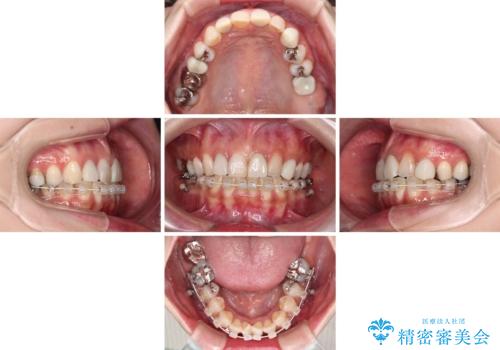

- 長年むし歯を放置してしまっているとのことで来院された患者様です。

神経が除去されている歯、根管治療の必要な歯、むし歯の非常に大きな歯に対してオールセラミッククラウンにて補綴治療を行うこととしました。

インプラント部は治癒待ちの期間が長くなるため、その期間を利用して下顎の叢生を解消し、より理想的な咬み合わせで補綴治療を行うこととしました。

途中通院されなかった時期が何度かあったため、初診から4年以上の年月がかかりましたが、比較的スムーズに治療を進めることができました。

下顎前歯の歯列を整えたことで、上顎前歯の咬み合わせが安定し、自然な口元に仕上げることができました。